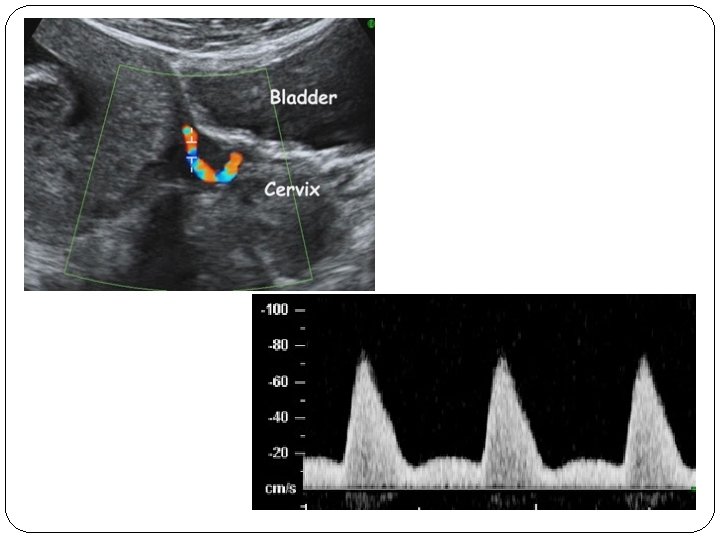

�measurement of the uterine artery pulsatility index (PI) at 11 -13 weeks' gestation in combination with maternal history(inc) mean arterial pressure(inc) serum PAPP-A(dec…>inc) placental growth factor (PLGF) (dec…>inc) �The factors in the maternal history that appear to make a significant independent contribution to the preeclampsia risk assessment included maternal BMI, age, ethnicity, smoking, and parity.

� early rather than late preeclampsia is associated with an increased risk of perinatal mortality and morbidity and both short-term and long-term maternal complications. � Combination of the above mentioned risk factors was 90% shown to predict of early preeclampsia, 35% of late preeclampsia, and 20% of gestational hypertension. � This compares favorably with screening based on 30% maternal history alone where only of early and 20% of late preeclampsia are predicted for a 5% false positive rate.